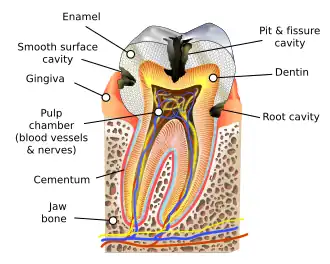

| Destruction of a tooth by dental caries and disease | |

Tooth decay, also known as caries,[a] is the breakdown of teeth due to acids produced by bacteria.[6] The resulting cavities may be many different colors, from yellow to black.[1] Symptoms may include pain and difficulty eating.[1][2] Complications may include inflammation of the tissue around the tooth, tooth loss and infection or abscess formation.[1][3] Tooth regeneration is an ongoing stem cell–based field of study that aims to find methods to reverse the effects of decay; current methods are based on easing symptoms.

The cause of cavities is acid from bacteria dissolving the hard tissues of the teeth (enamel, dentin, and cementum).[4] The acid is produced by the bacteria when they break down food debris or sugar on the tooth surface.[4] Simple sugars in food are these bacteria's primary energy source, and thus a diet high in simple sugar is a risk factor.[4] If mineral breakdown is greater than buildup from sources such as saliva, caries results.[4] Risk factors include conditions that result in less saliva, such as diabetes mellitus, Sjögren syndrome, and some medications.[4] Medications that decrease saliva production include psychostimulants, antihistamines, and antidepressants.[4] Dental caries are also associated with poverty, poor cleaning of the mouth, and receding gums resulting in exposure of the roots of the teeth.[6][8]

In most people, disorders or diseases affecting teeth are not the primary cause of dental caries. Approximately 96% of tooth enamel is composed of minerals.[44] These minerals, especially hydroxyapatite, will become soluble when exposed to acidic environments. Enamel begins to demineralize at a pH of 5.5.[45] Dentin and cementum are more susceptible to caries than enamel because they have lower mineral content.[46] Thus, when root surfaces of teeth are exposed from gingival recession or periodontal disease, caries can develop more readily. Even in a healthy oral environment, however, the tooth is susceptible to dental caries.

Enamel

Tooth enamel is a highly mineralized acellular tissue, and caries act upon it through a chemical process brought on by the acidic environment produced by bacteria. As the bacteria consume the sugar and use it for their own energy, they produce lactic acid. The effects of this process include the demineralization of crystals in the enamel, caused by acids, over time, until the bacteria physically penetrate the dentin. Enamel rods, which are the basic unit of the enamel structure, run perpendicularly from the surface of the tooth to the dentin. Since demineralization of enamel by caries follows the direction of the enamel rods, the different triangular patterns between pit and fissure and smooth-surface caries develop in the enamel because the orientation of enamel rods are different in the two areas of the tooth.[76]

Dentin

Sclerotic dentin

The structure of dentin is an arrangement of microscopic channels, called dentinal tubules, which radiate outward from the pulp chamber to the exterior cementum or enamel border.[81] The diameter of the dentinal tubules is largest near the pulp (about 2.5 μm) and smallest (about 900 nm) at the junction of dentin and enamel.[82] The carious process continues through the dentinal tubules, which are responsible for the triangular patterns resulting from the progression of caries deep into the tooth. The tubules also allow caries to progress faster.

Cementum

Affected hard tissue

Depending on which hard tissues are affected, it is possible to describe caries as involving enamel, dentin, or cementum. Early in its development, caries may affect only enamel. Once the extent of decay reaches the deeper layer of dentin, the term "dentinal caries" is used. Since cementum is the hard tissue that covers the roots of teeth, it is not often affected by decay unless the roots of teeth are exposed to the mouth. Although the term "cementum caries" may be used to describe the decay on the roots of teeth, very rarely does caries affect the cementum alone.